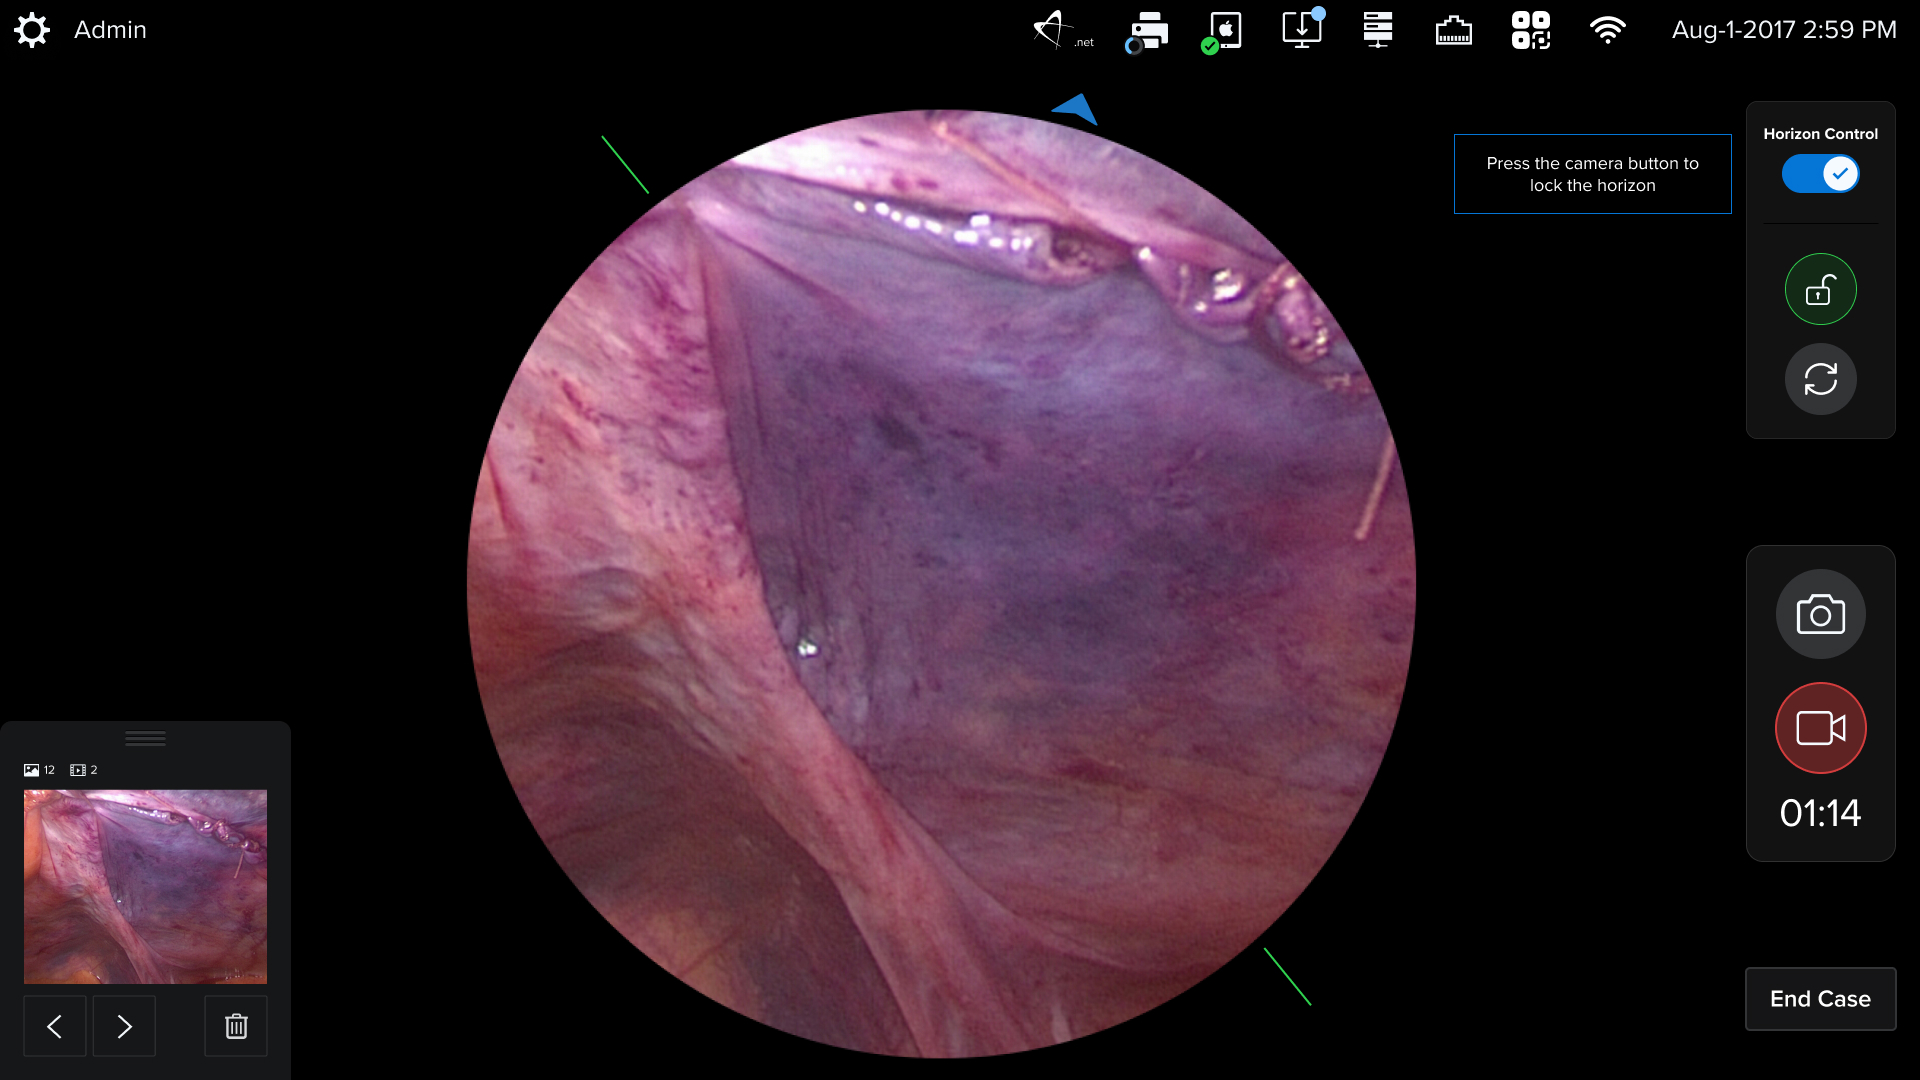

Watch how I brought digital designs to life with real medical hardware

HUD Design: Surgery-Ready Interfaces

Operating rooms aren't like offices. I designed interfaces specifically for heads-up displays, considering lighting, distance, and the critical nature of surgical procedures.